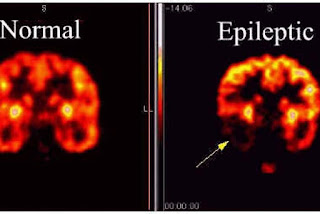

5. Epilepsi

Epilepsi adalah kelainan kronik yang disebabkan oleh impuls berlebihan dari sel-sel saraf dalam otak yang dicirikan oleh serangan mendadak dan berulang-ulang. Serangan dapat berupa sawan, hilang kesadaran beberapa saat, gerak atau sensasi aneh bagian tubuh, tingkah laku aneh, dan gangguan emosional. Serangan epilepsi umumnya berlangsung hanya 1-2 menit. Kemudian diikuti oleh kelemahan, kebingungan, atau kekurangtanggapan.

![]() |

| Gambar 2.6.5. Kondisi otak normal dan epilepsi |